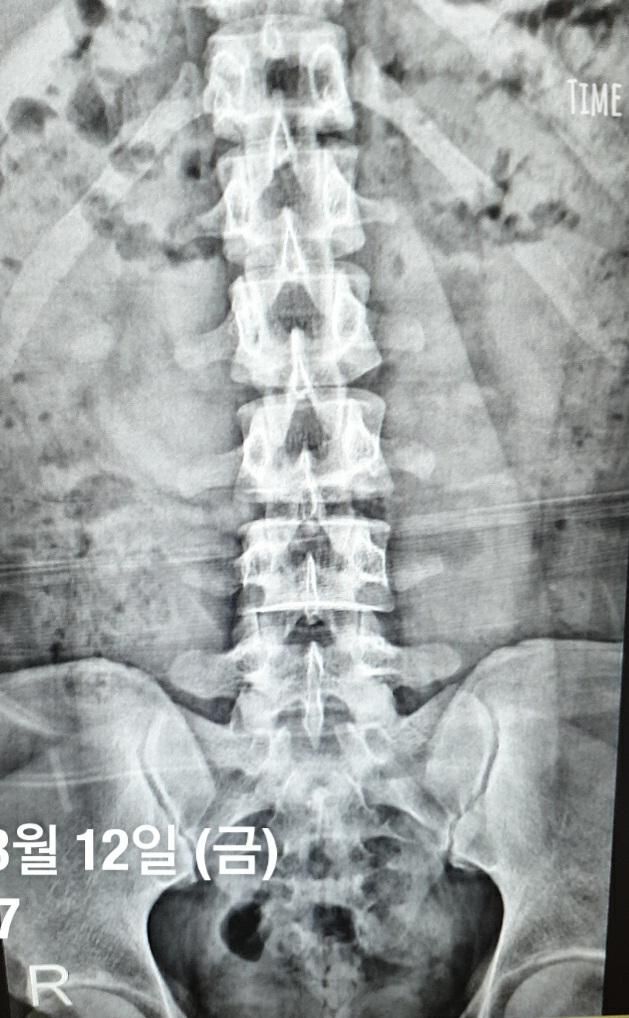

영상의학과 질문 과거 X-ray로 알 수 있는 것

신경과 질문에 과거 허리 X-ray를 통해 추측할 만한게 있을지 아하를 통해 질문했는데 정확한 진단은 영상 의학과에 물어보는게 좋을 거 같다고 하셔서 올려봅니다.

동네 병원에서 찍었던 이 단순한 정면 허리 X-ray 사진으로 추측해볼만한게 있을까요?

나중에 다른 종합 병원에서 디스크 진단 받고 치료 받았습니다만

물론 강척이든 디스크든 있다고 해도 완전 초기일 때라 보일 거 같지 않고, 단순 정면 X-ray로 알 수 있는 정보는 딱히 없을 듯 하지만 혹시나 하는 마음에 질문을 올려봅니다.

강직성 척추염 양상의 허리 X-ray영상으로는 보이지 않습니다.

다만 궤양성 대장염, 포도막염 등의 증상으로 미루어 보았을 때 X-ray에서 관찰되지 않더라도 진단은 받아보시는 것이 좋습니다.

말씀하신 통증이 심하지 않았을 때 촬영한 X-ray임을 미루어 볼 때 , 추적관찰 목적의 x-ray촬영이 도움이 될 수 있겠습니다.